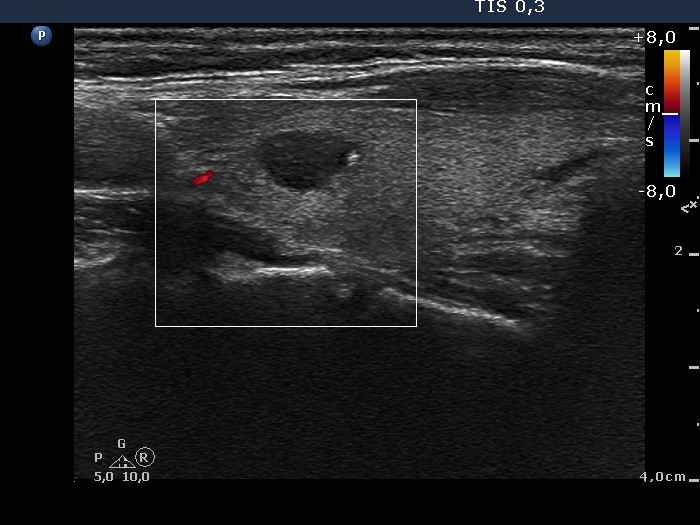

Benign nodular hyperplasia - Case 55. (ultrasonographic picture 9)

Left lobe, longitudinal scan, color Doppler mode. The hypoechogenic lesion is avascular.